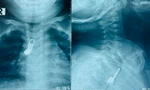

![]() |

| Bệnh viện Chợ Rẫy đã thực hiện hơn 1.100 ca ghép thận trong 30 năm qua. |